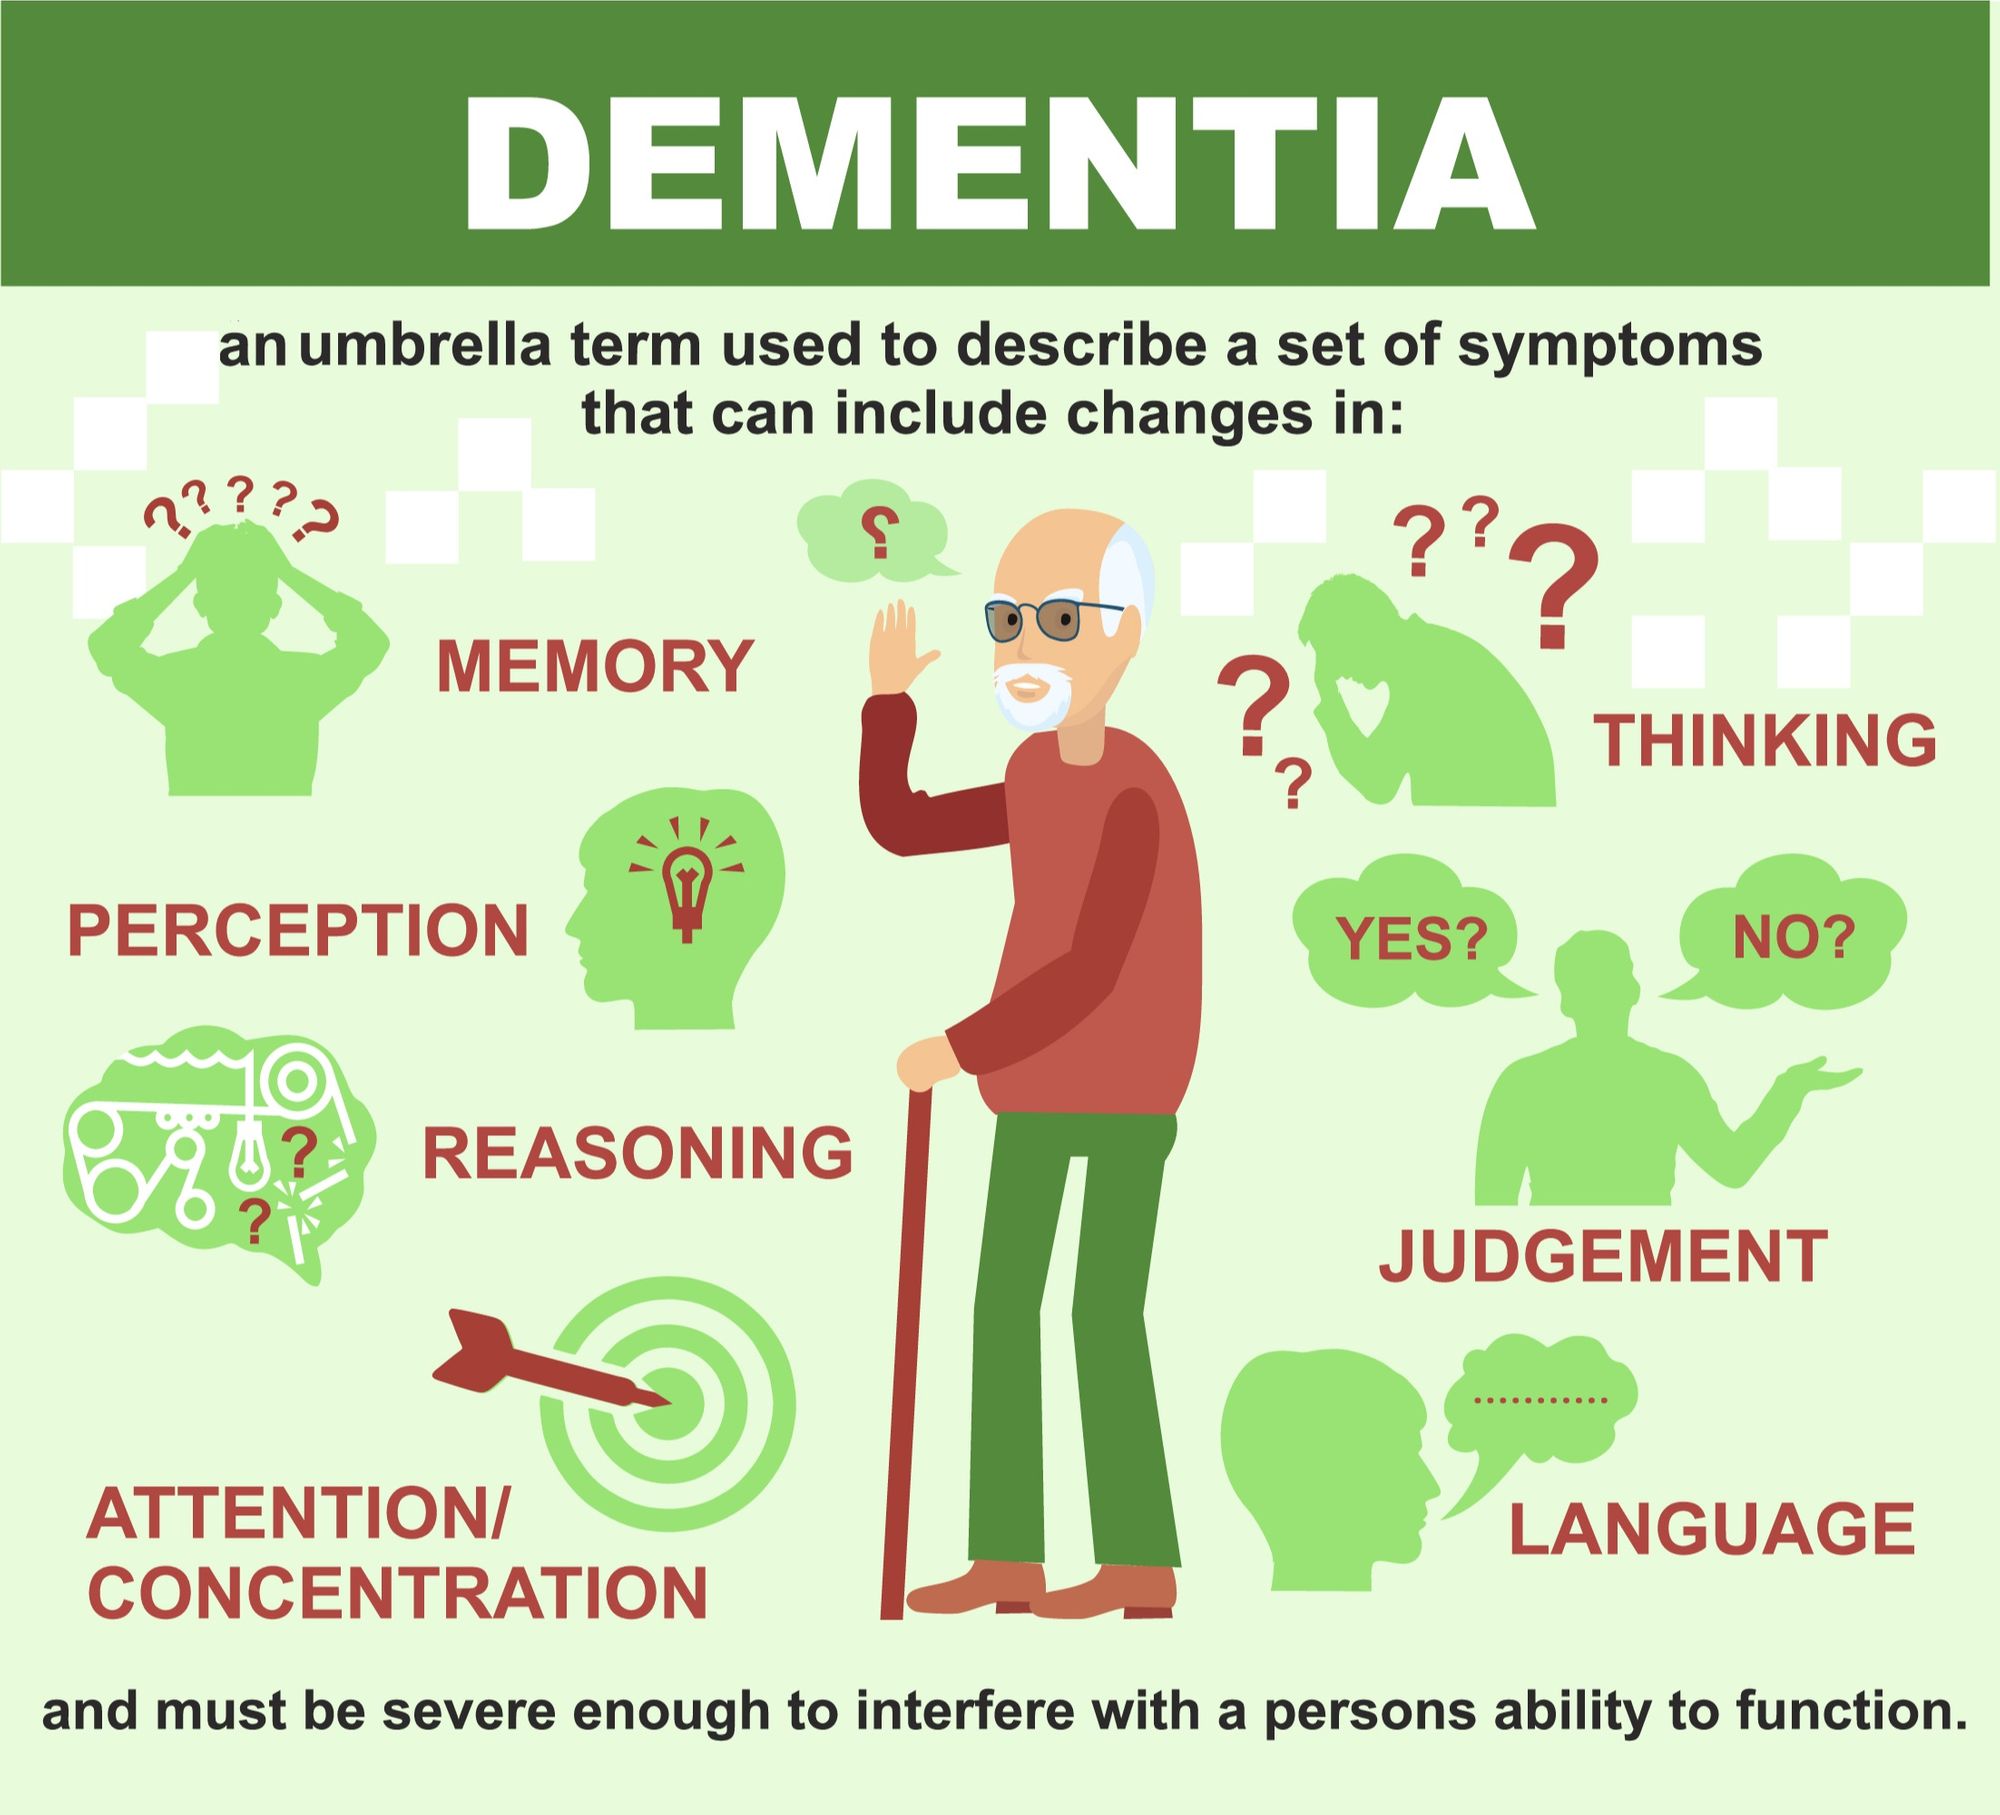

Dementia is an umbrella term. It describes the symptoms that occur when …